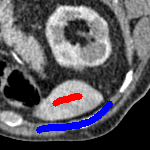

3 Alternative Selective Segmentation Models

We now introduce two recent methods that incorporate user input to perform selective segmentation. Each involves input in the form of foreground/background regions to indicate relevant structures of interest. An example of this can be seen in Fig. 18, where red regions indicate foreground and blue regions indicate background. We compare against the work of Nguyen et al. Nguyen:12 , which uses a similar convex relaxation framework to the proposed approach, and Dong et al. SRW , which uses a variation of the random walk approach. We summarise the essential aspects of each approach in the following.

7.4 Alternative Selective Methods

In order to further establish the robustness of our method, we now introduce the results of testing our approach against competing interactive segmentation methods on a larger data set. The results are presented in Fig. 17, showing a boxplot of accuracy in terms of TC on a set of 30 CT images (excluding outliers). The target structure we consider is the spleen, as this consists of a relatively homogeneous foreground, appropriate for the approach considered. The data has been manually contoured providing ground truth data for the image set. We compare CAC Nguyen:12 and SRW SRW against our method with five variations of user input for each image. It is worth emphasising here that the input used in the tests is identical for each approach and was not refined in any way. It was designed to mimic what a user, unfamiliar with each approach, might select intuitively. A representative example for three images is shown in Fig. 18. This shows foreground (red) and background (blue) user input regions. For our method, we define the red region as as discussed in §1 and enforce hard constraints on the blue region. We refer to the results of the proposed approach using this input as Ours (i). We also include results of randomising the user input in an identical way to §7.3. For each image we generate 1000 simulated user input choices, which we present as Ours (ii). It is important to note that the difference between Ours (i) and (ii) is only the definition of . The method and parameters are fixed between each.

The performance of CAC Nguyen:12 is very good, as shown in Fig. 17. We have included an additional figure to highlight the difference between CAC and Ours (i) and (ii) more precisely. This is shown in Fig. 19 (this is the same as Fig. 17 with TC restricted to [0.8,1]). Here we can see that the proposed approach has a slightly better median (0.96 compared to 0.94) and is generally more consistent than CAC. This is particularly evident when considering the worst TC results of CAC () against ours ().

In Fig. 17 it can be seen that our method exceeds the performance of SRW by a large margin (0.66 compared to 0.95). One possible reason for this is that the input used, as displayed in Fig. 18, is restricted to be as intuitive as possible. SRW is capable of achieving improved results with more elaborate foreground/background input. However, it is generally reliant on a trial and error approach which is not ideal in practice. This highlights an important advantage of our method. It is able to achieve a high standard of results with simple user input. This is reinforced by considering Ours (ii), where the results of 30000 random variations of the user input does not cause a drop off in accuracy compared to the 150 manual user input selections. Again, this can be seen more clearly in Fig. 19. In fact, the results for the proposed approach with the random input are slightly better than with the manual input. This underlines the robustness to user input in the model, which is a vital aspect of selective segmentation.